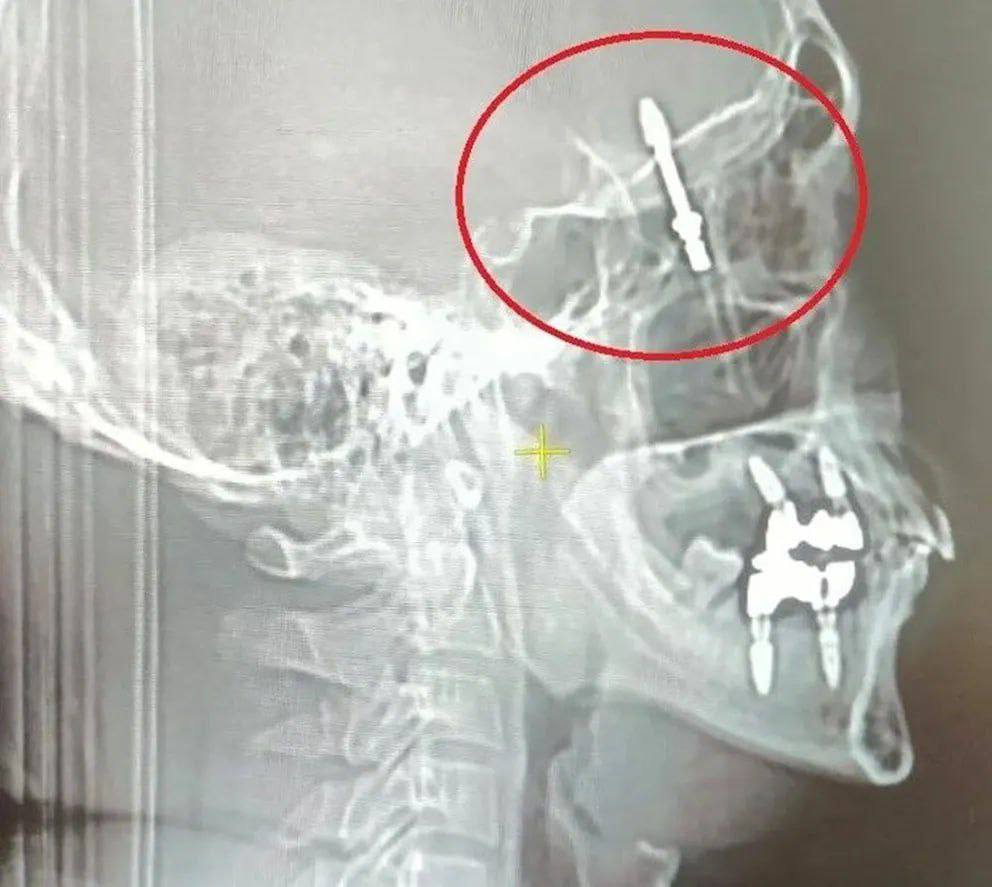

40-летний мужчина в Турции обратился в частную клинику, чтобы ему вырвали больной зуб и установили вместо него имплант.

Во время операции оборудование для установки импланта вышло из строя и врач решил действовать вручную, однако завинтил имплант с такой силой, что проломил кости черепа и попал в мозг. После этого мужчину отвезли в больницу.